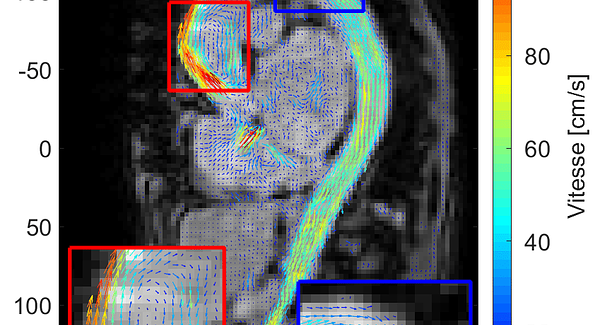

Jeudi 10 juin - Épisode 1 “La preuve en images” : Cet épisode décrira le parcours de la détection d’un cancer à travers différents examens d’imagerie.